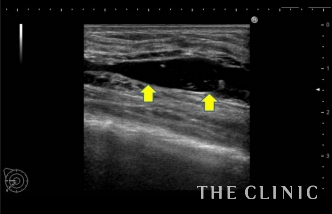

この方は施術を受けたクリニックでヒアルロン酸溶解の処置を受けられているのですが、まだ残っている気がするためエコー検査に来院されました。

実際に診てみると、確かにヒアルロン酸が残っていて、黒い塊として確認できました。

触診では困難なため、リアルタイムで映し出されるエコーの映像を確認しながら、ヒアルロン酸(しこり内)に確実に溶解液(ヒアルロニダーゼ)を注入します。

これにより、ヒアルロン酸の加水分解が始まり数十秒でジェル状に。それを吸引除去しました。

画像の矢印の少し上、真ん中から右端へ入っている白い線が先程の治療で使った吸引管ですが、ヒアルロン酸を除去したことにより、施術直後からしこりがなくなっていることが確認できます。